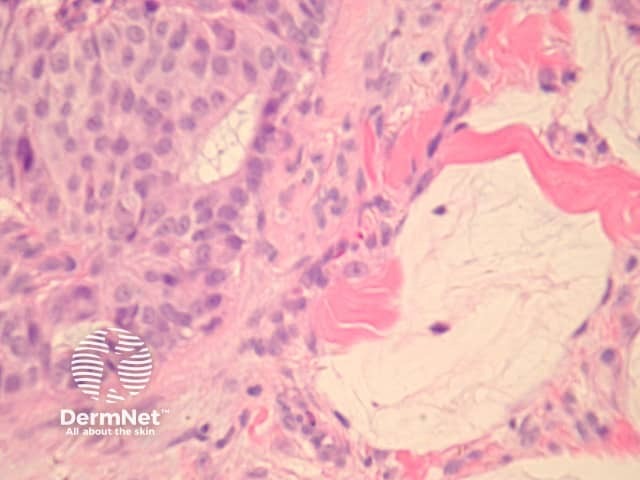

In EMPSGC, sections show a dermally based tumour mass under an intact epidermis. It consisted predominantly of nodules of the tumour as well as cystic spaces somewhat reminiscent of a hydrocystoma (figures 1, 2, 3). Higher power reveals a uniform population of round-to-oval cells with fairly abundant pale and pink cytoplasm. The nuclei have fine stippled chromatin consistent with neuroendocrine differentiation (figure 4). Areas transitioning into mucinous carcinoma, with tumour islands floating in copious mucinous material may be seen (figure 5).

Figure 5